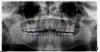

Пошел, в частности из-за боли в зубе отмеченном синей рамкой на

приложенном снимке. В одной клинике мне сказали что поможет только

депульпирование и коронка, однако в той которой лечился в итоге,

сказали что на прицельном снимке (снимка до лечения у меня нету) кариес еще не затронул

пульпу. Гарантии 100% нет, только при вскрытии будет ясно можно ли

Это была предыстория :) Обратиться я хочу вот по какому вопросу. На

отмеченных красными квадратами местах на снимке, мне сказали что тоже

развивается контактный кариес. В нижем квадрате один зуб вылечили, а

на другом сказали что пока просто побеление (?) эмали.